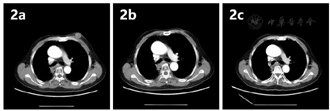

2021年9月11日胸腹平扫+增强CT提示:(1)食管癌治疗后,请结合临床及老片;(2)考虑右肺放疗后改变,右下肺结节较2021年7月22日片明显缩小;右侧胸膜增厚;(3)升主动脉增粗,主动脉及冠状动脉粥样硬化;(4)右肾小囊肿,右肾结石;(5)左肾未见明显显示,左肾上腺结节、腹腔及腹膜后结节、左胸壁皮下结节及肝右叶异常强化影,较前片2021年7月22日片相仿(图1,图2,图3)。